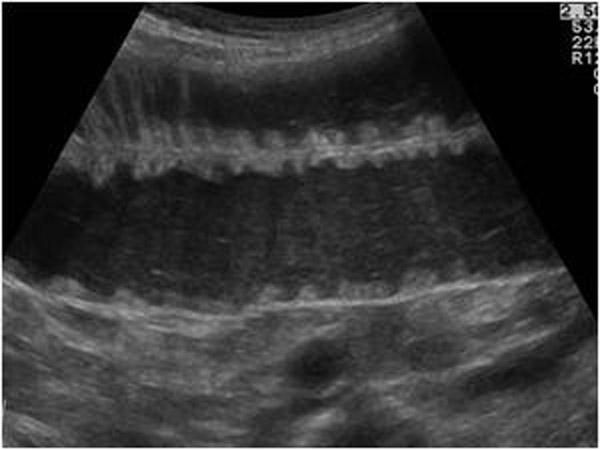

Chronic Pancreatitis

Ongoing inflammation that results in permanent damage

N & V

flatulence

weight loss

Chronic Pancreatitis

Ongoing inflammation that results in permanent damage